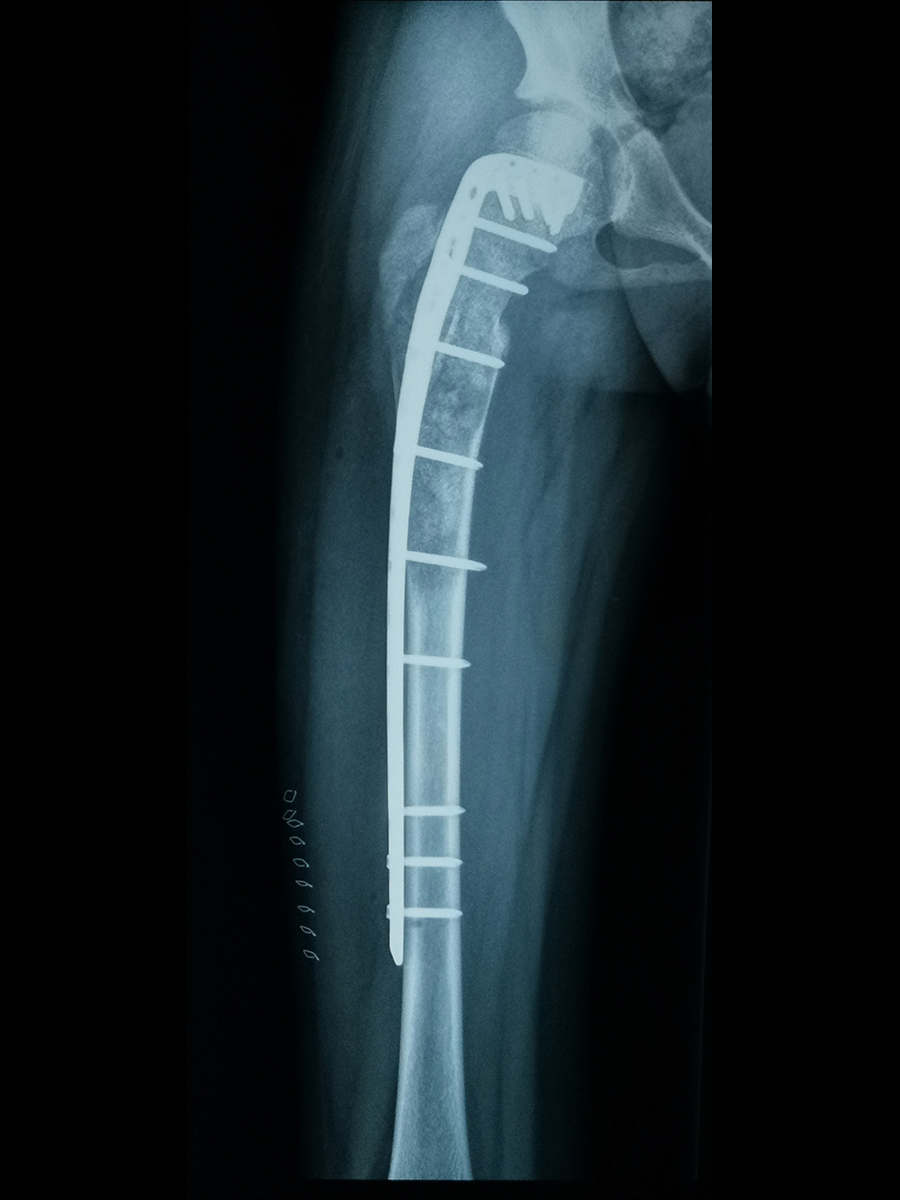

摘要:骨纤维结构不良常见于青少年及儿童,本病可导致肢体畸形和疼痛逐渐加重,但常以骨折为最早出现的症状。本文中18岁的男性患者主诉大腿疼痛,活动时加重,休息可以缓解,通过辅助检查以及病史,高度疑似骨纤维结构不良,建议患者行病灶刮除植骨手术治疗+内固定手术治疗。术后大腿疼痛明显缓解,术后6个月可以完全弃拐行走。

【治疗方案】手术治疗(病灶刮除植骨手术+内固定手术)

患者入院后进一步检查MRI,显示双侧股骨颈和粗隆部都可见髓内异常信号。从MRI结果来看高度疑似骨纤维结构不良,但是最终确诊需要依靠病理学诊断,病理是确诊的金标准。和患者以及家属沟通了病情以及治疗方案后,患者最终接受了病灶刮除植骨手术治疗+内固定手术治疗,手术中将病灶完全刮除,并植入自体髂骨,根据术后病理确诊为骨纤维结构不良。

患者手术后大腿疼痛明显缓解,术后2周拆线顺利出院。患者出院后定期在门诊复查,术后6周内患者可以扶拐行走。术后3个月时,拄单拐基本可负重行走,大腿局部没有出现不适症状。术后6个月可以完全弃拐。术后1年左右,待骨完全愈合后,可取出内固定。

骨纤维结构不良常会侵犯骨皮质,导致局部骨质强度下降,手术将病变刮除后,骨骼强度会进一步下降,因此患者常常需要辅助内固定保护,避免术后出现骨折。骨纤维结构不良术后常需要拄拐一段时间,具体时间取决于病损刮除的范围。此外,虽然骨纤维结构不良属于良性病变,极少恶变,但是患者术后也需要半年左右复查1次。患者在日常生活中也要注意多进食含钙高的食物,以及多晒太阳。18岁小伙手术后不适症状得到缓解,手术效果良好,我为患者感到十分高兴。